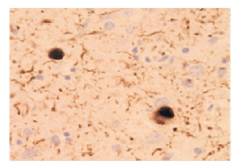

免疫染色画像 (路易体痴呆症的大脑切片)

数据提供: 东京大学大学院医学系研究科 岩坪威 |

与帕金森氏病、路易体痴呆症(DLB)等神经细胞特异性出现的路易体,包含丝氨酸129残基特异性磷酸化的α-突触核蛋白。 本产品不与正常α-突触核蛋白反应,识别堆积的磷酸化α-突触核蛋白,可提供路易体相关的病理研究。 |